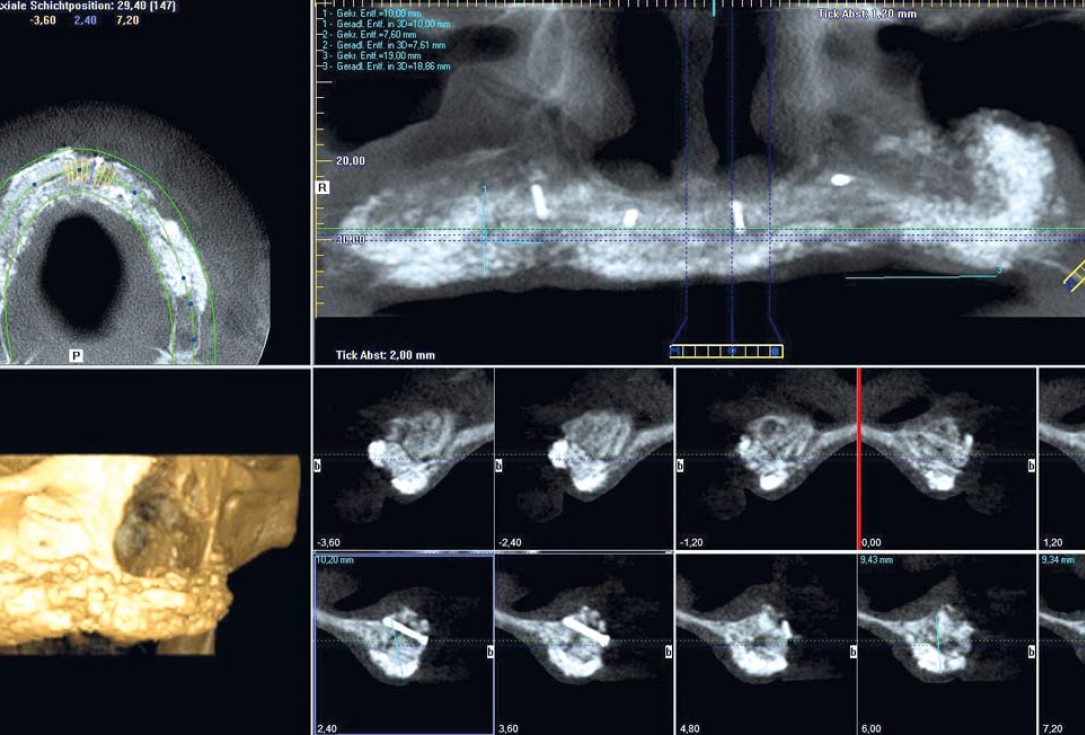

11/23 - Radiological situation after augmentation

Full arch reconstruction of the maxilla with maxgraft® bonebuilder - Dr. M. Erbshäuser

12/23 - Radiological situation after augmentation

13/23 - Radiological situation after augmentation